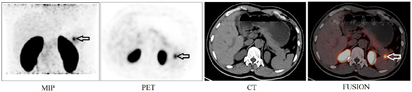

低血糖时同步测血葡萄糖1.73 mmol/L(参考范围:3.89~6.11mmol/L,以下同)、血清胰岛素10.44 μIU/ml(1.9~23μIU/ml)、C肽4.25 μg/L(1.1~4.4μg/L)。饥饿试验:血葡萄糖1.97 mmol/L(3.89~6.11mmol/L)、血清胰岛素11.56 μIU/ml(1.9~23μIU/ml)。胸部CT、全腹彩超、甲状腺彩超及胰腺MRI平扫+增强均未见明确异常。68Ga-exendin-4 PET/CT显像(图1)示胰尾一结节状放射性摄取增高灶,直径约1.0 cm,SUVmax = 9.8,同机CT示相应部位为等密度影;余胰腺组织呈弥漫型轻度放射性摄取,诊断胰尾胰岛素瘤。